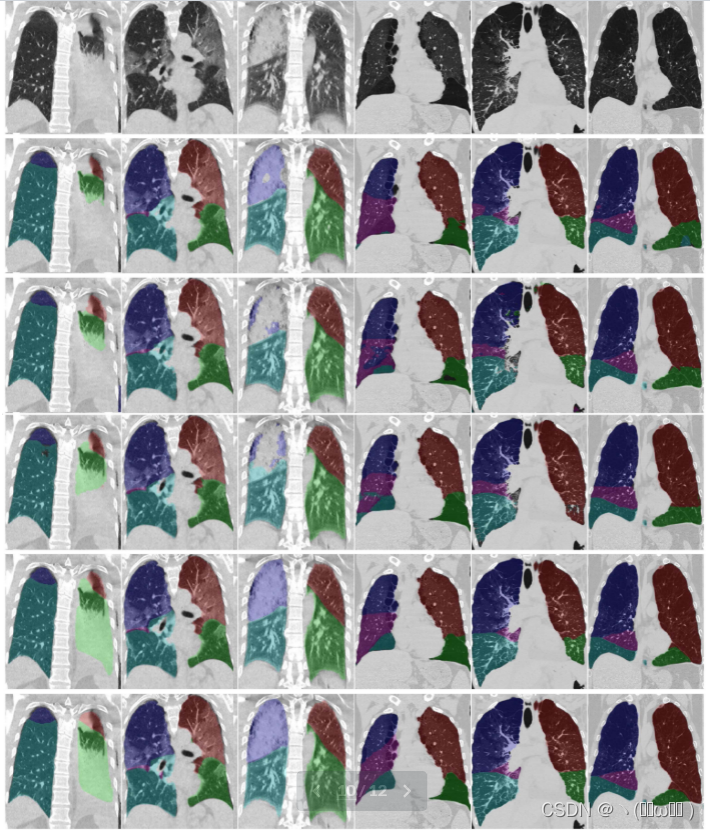

图 5 从上到下显示了 3D U-Net、PDV-Net [13]、FRV-Net [12] 和 RTSU-Net 的结果。为了比较,底部行提供了参考分段。我们选择了 3 例 COPD(4-6 列)和 3 例 COVID-19 病例(1-3 列),具有不同程度的病理和解剖变异。我们观察到所有方法通常不会产生肺的过度分割。通过捕获特征依赖关系,我们看到所提出的方法通常会生成更平滑的肺叶边界,甚至能够在肺充满液体时推断出近似正确的肺叶形状(第 1 列)。

图5:六个代表性测试用例的分割结果的定性比较。左三列显示 COVID-19 病例,右三列显示 COPD 病例。从上到下:输入图像、3DU-Net 基线、PDV-Net、FRV-Net、提出的 RTSU-Net 和分割参考。 蓝色右上,紫色右中,深绿色右下,红色左上,绿色左下叶。

在对 COVID-19 导致的重症肺炎患者的扫描中进行肺叶分割并非易事。在这项工作中,我们仅使用 370 个 COVID-19 CT 扫描进行训练。由于对 4000 次 COPD 扫描进行了预训练,我们仍然使用少量训练集获得了良好的结果,并且我们能够提供对毛玻璃、固结和疯狂铺路的存在稳健的肺叶分割。肺叶分割是在 COVID-19 CT 扫描中准确量化肺损伤的重要先决条件。图 5 显示标准 3D U-Net(第 2 行)、PDV-Net(第 3 行)和 FRV-Net(第 4 行)可能会漏掉固结区域(第 3 列),而 RTSU-Net 准确地找到了肺叶。当该肺叶完全充满胸腔积液(第一列)时,RTSU-Net 的性能也相当不错。

尽管如此,我们也看到,有时所提出方法的分割边界不正确(第 3 列,右上叶在叶边界向肩部显示出轻微的过度分割),我们假设更大的训练集将进一步提高性能,特别是对于在当前训练扫描中尚未很好表示的严重病理变化的病例。尽管如此,这里提供的结果足以进行进一步分析,我们相信它们将在自动每叶严重性评分中证明是有用的。这是未来研究的课题。